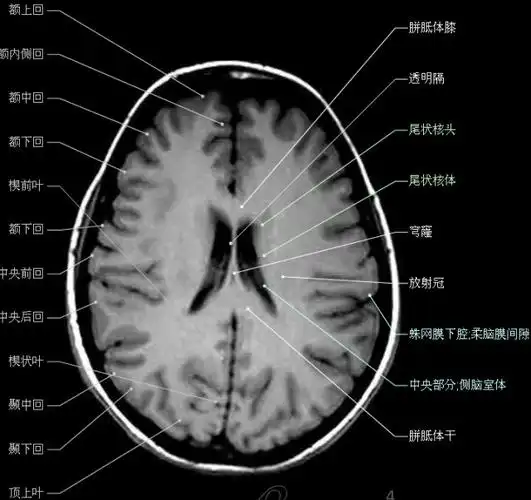

大集合颅脑轴向结构解剖图